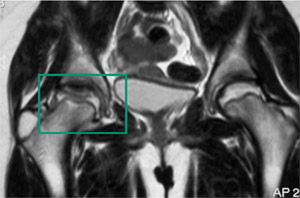

- ressonância nuclear magnética (RNM) do quadril:

vascularidade reduzida da cabeça do fêmur pode ser observada no início da doença; achatamento, esclerose e, por fim, fragmentação e colapso da epífise femoral, com alargamento do colo do fêmur